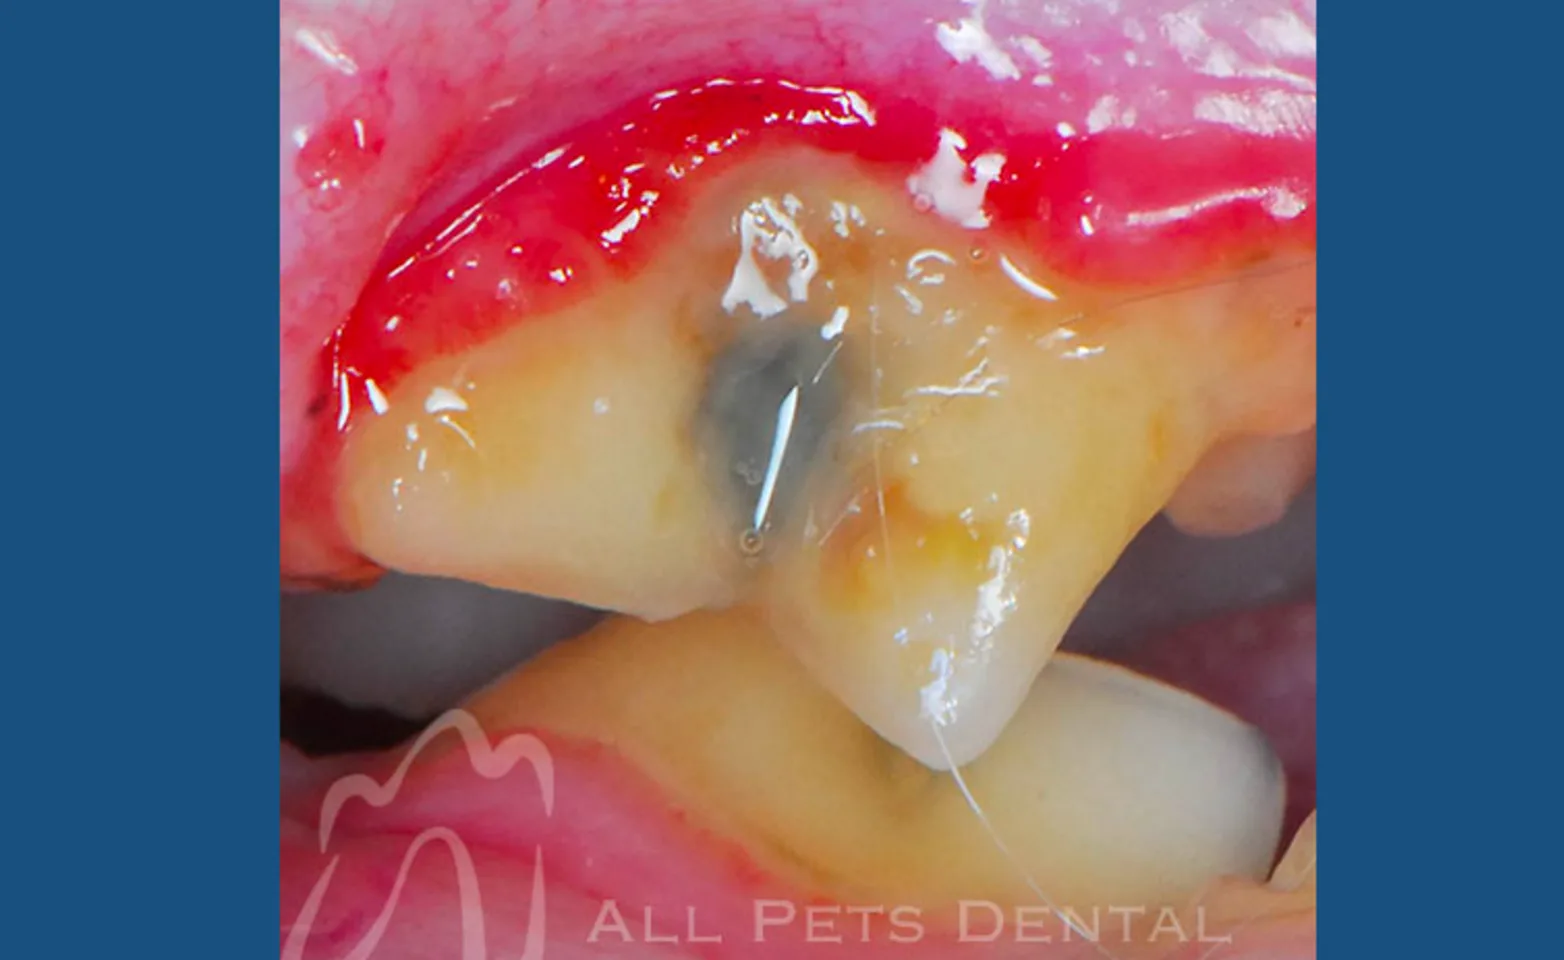

Stage 3

In stage 3 moderate periodontal disease, painful loss of tooth support has progressed to the point that either advanced periodontal procedures or extraction is needed.